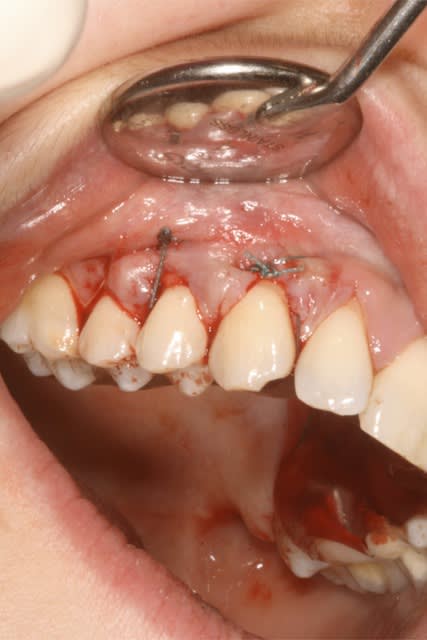

27/03/2013 à 15h34

Salut Olivier, je comprends ce que veut dire Tilc.

Tunel car pas de lambeau a proprement parlé, puis LDC car traction de l'ensemble en direction corronaire.

J'ai fait la même chose, grace à tes précieux conseils.

Mais pour toi il s'agit certainement d'une erreur de terminologie non?

(ps: la dernière photo est à + 2ans )

Img 6444 ftxtdt - Eugenol

Img 6445 nfl76o - Eugenol

Img 6447 rkmldx - Eugenol

Img 7127 weu05p - Eugenol